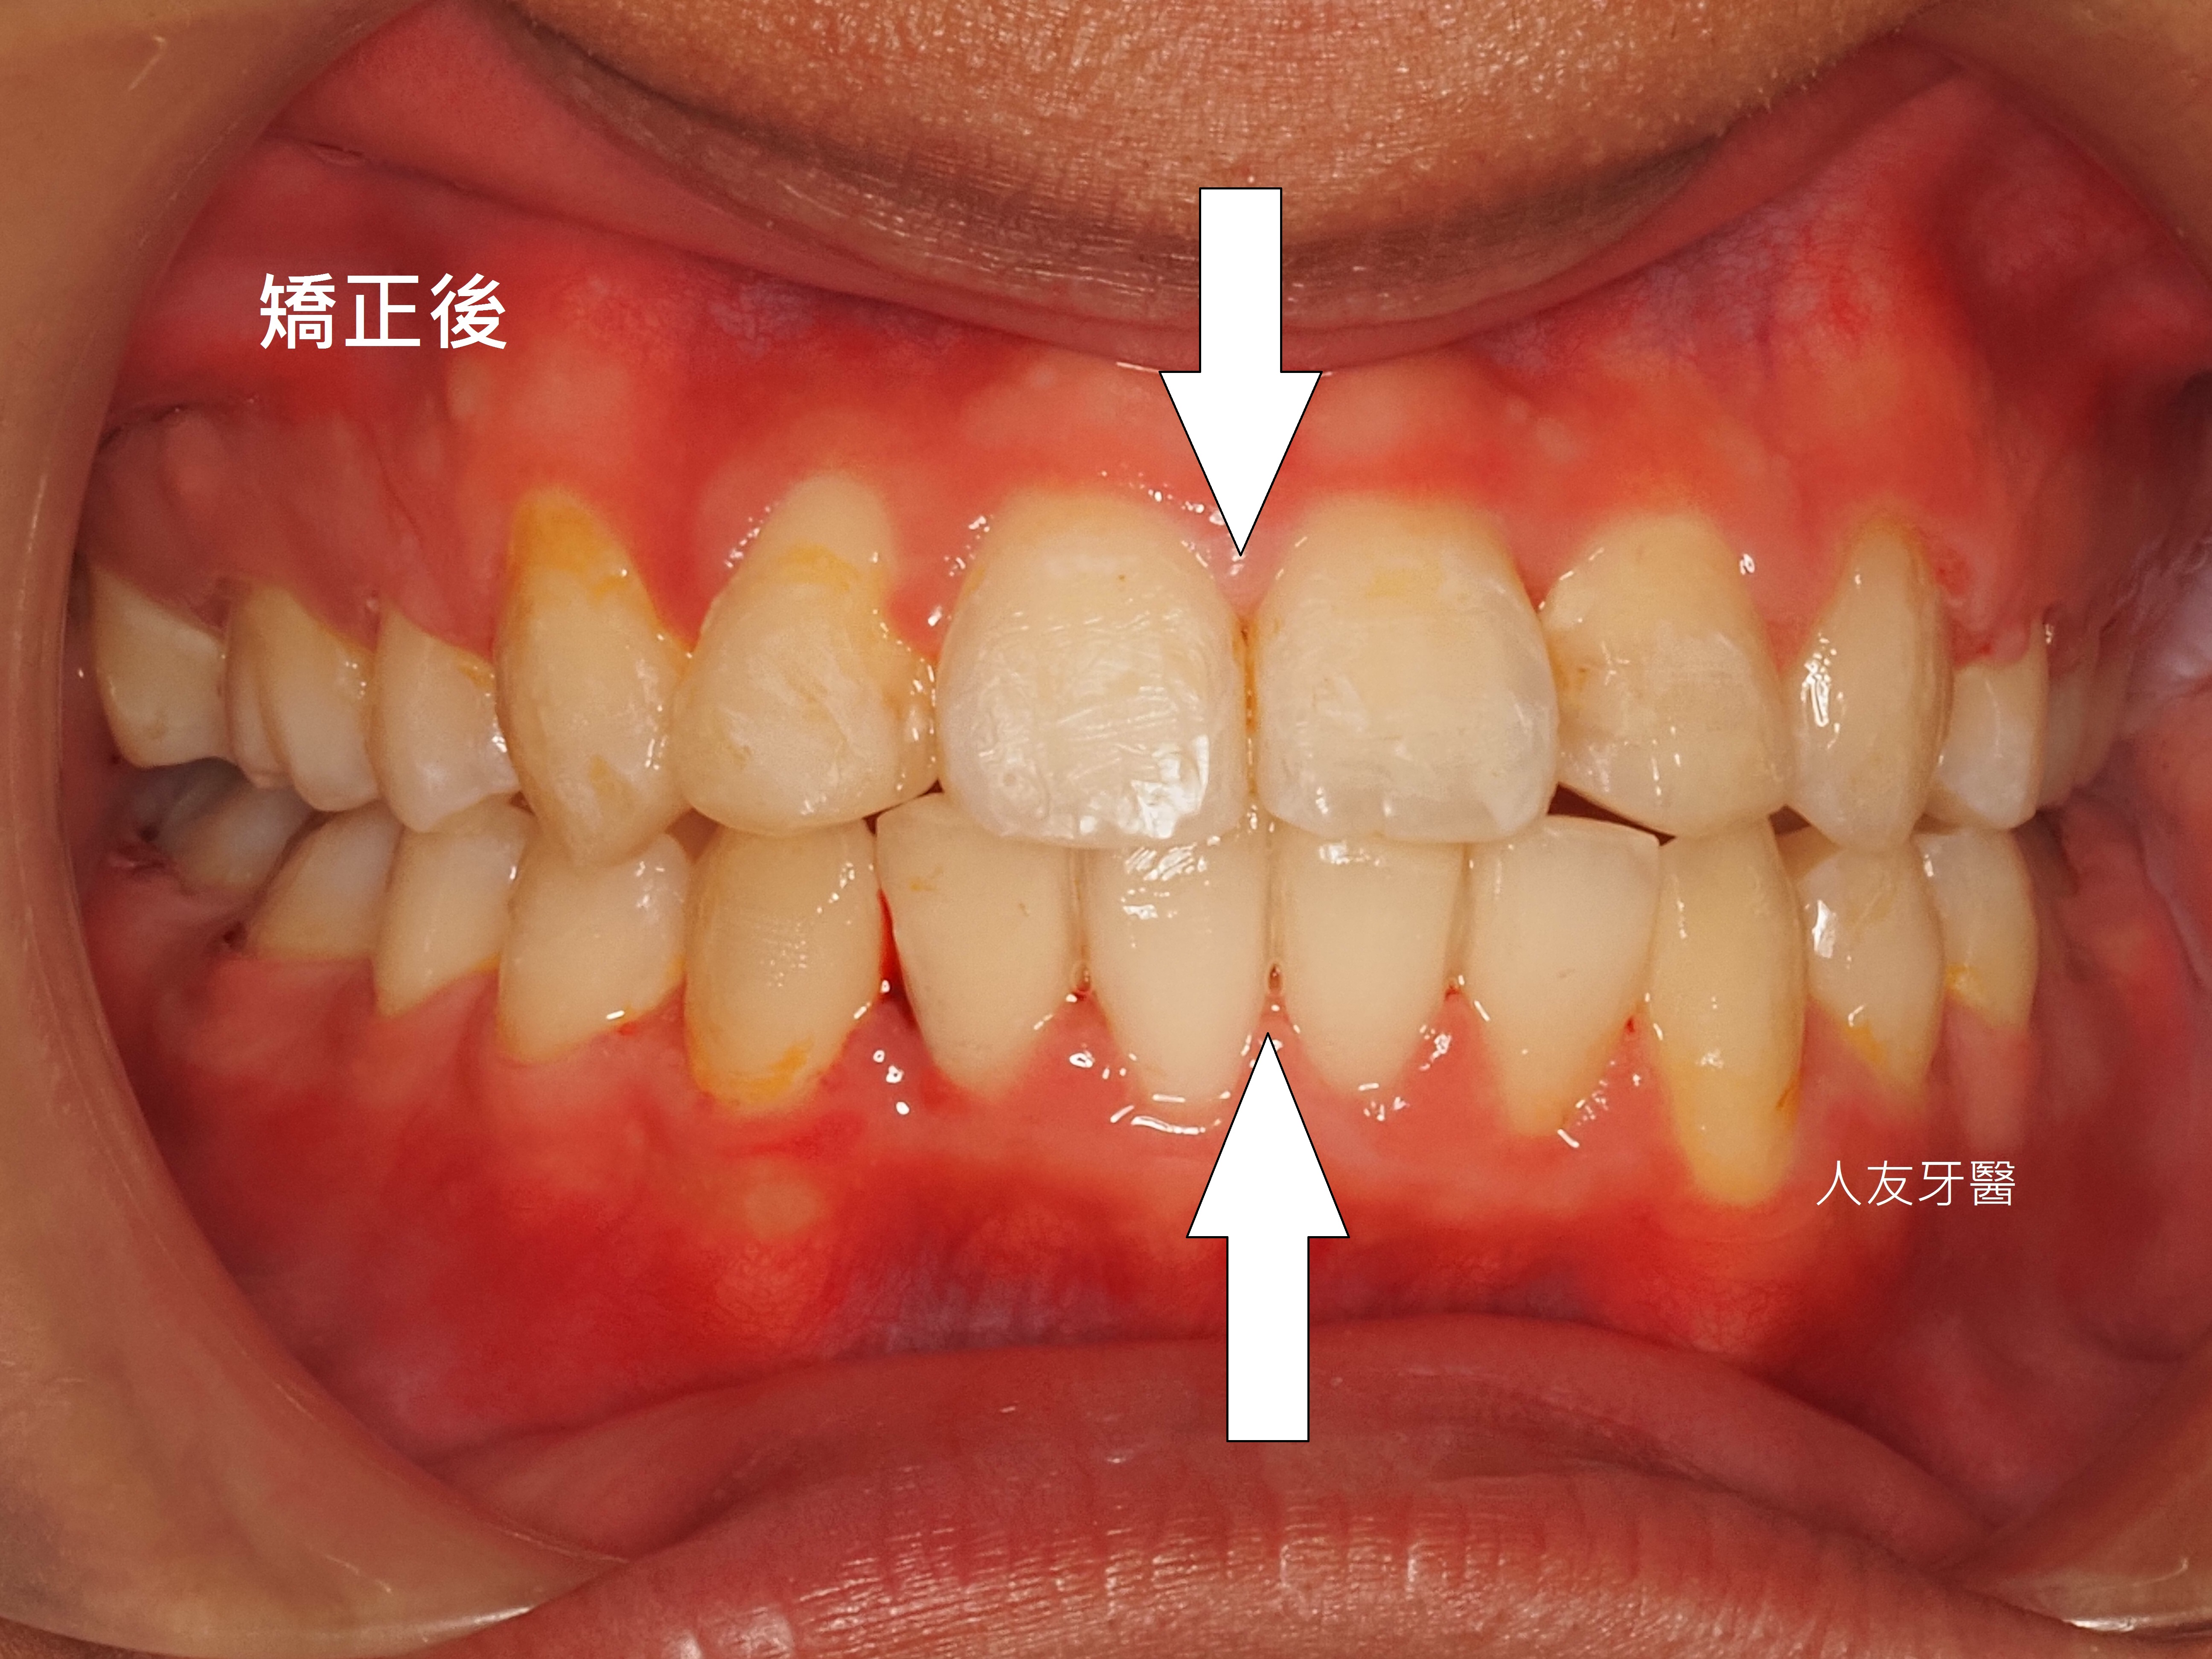

左右兩側的牙齒數量、牙齒凌亂程度、牙齒大小比例關係,都是會影響牙齒中線的原因。

牙齒中線偏移的缺點(上兩圖):

臉部不協調: 上排牙齒中線與臉部中線不對齊,會讓臉型看起來歪斜,視覺上不美觀。

下巴視覺上翹: 中線偏移常伴隨下巴歪斜,使下巴看起來向上翹起。

咬合不正: 牙齒排列不齊,導致咬合關係不佳,影響咀嚼功能。